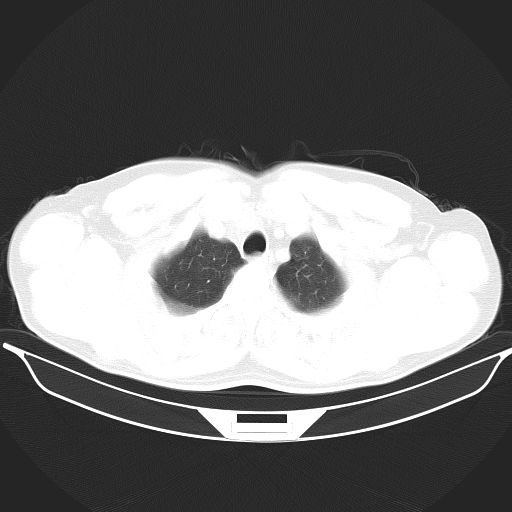

标题: CT25490:男,40岁,体检发现;无其它不适。 [打印本页]

标题: CT25490:男,40岁,体检发现;无其它不适。

考虑右下肺周围性肺癌并肺内多发转移,纵隔淋巴结转移!

考虑过敏性肺炎,建议抗炎后复查,转移瘤及tb待排

支持 !考虑右下肺周围性肺癌并肺内多发转移,纵隔淋巴结转移,(气管前腔静脉后,隆突下,主动脉弓下都有了)